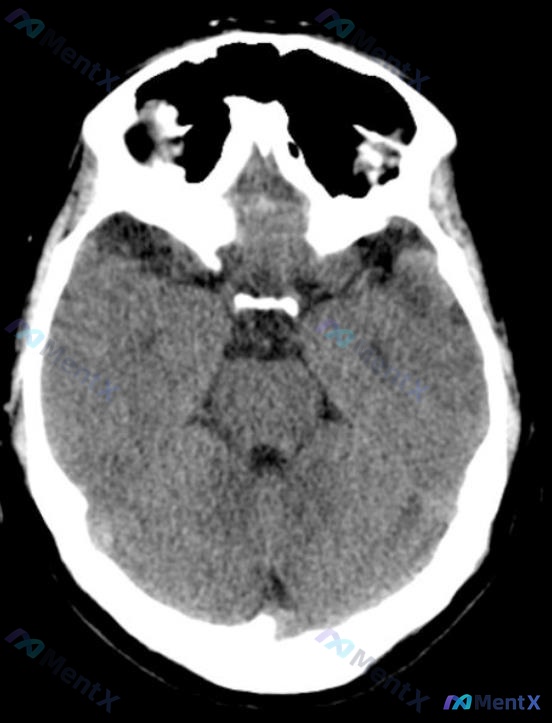

整理了一份有点“矛盾”的病例资料: - 临床定位指向左侧小脑+脑桥受累(有相应的神经功能缺损描述) - 但头部CT平扫(非增强)报告写的是:未见明显低密度灶,排除大面积脑梗死,中线结构正常,无出血 第一眼看到这种“临床-影像不一致”的情况,大家会怎么考虑? 这份资料里其实有一个经典的神经科陷阱,尤其...